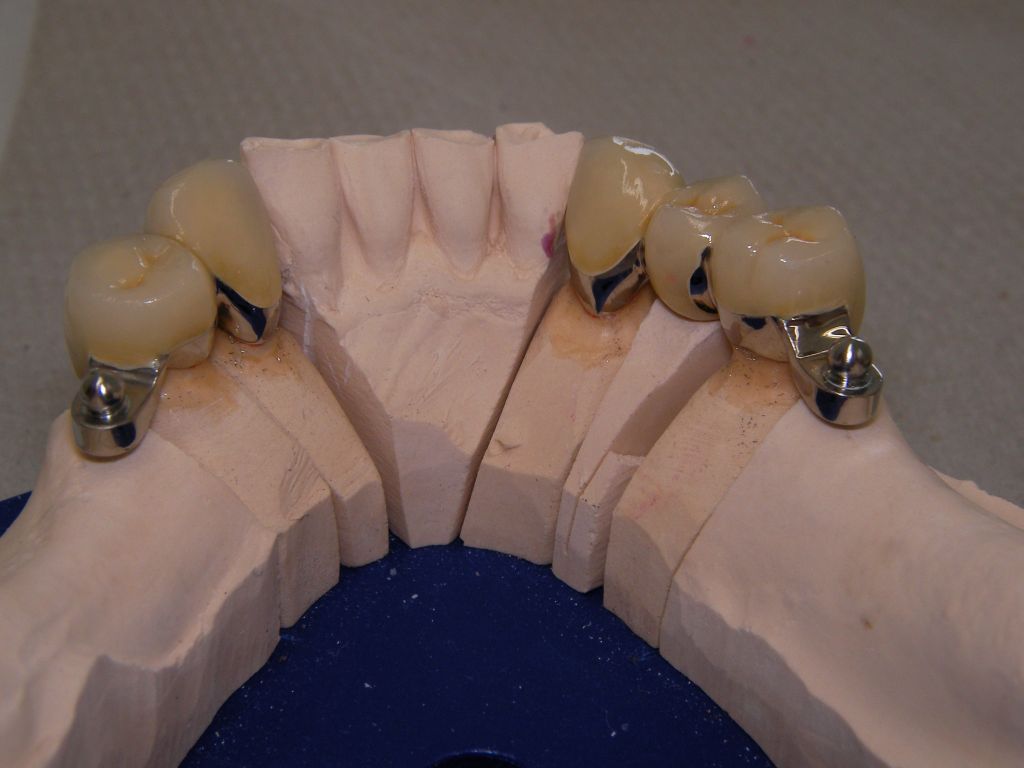

Die Bilder können alle angeklickt werden! Das Hauptproblem dieses Falles lag im Oberkiefer - die über die Jahrzehnte abgeknirschten, kurzen Zähne erschweren Kronen, die durch eine Prothese belastet werden können. Die gewählte Lösung besteht darin, die Zähne nur rundherum zu beschleifen, aber nicht mehr zu kürzen und die Prothese mit einem Druckknopfsystem an die Zähne anzukoppeln, das ein "Spiel" aufweist, so daß die Prothese nicht als Hebelarm auf die schwachen Restzähne wirken kann. Rechts die beschliffenen Zähne kurz vorm Zementieren der Kronen. |

Links das Bild zeigt das Metallgerüst, das später mit Keramik verblendet wurde. Um eine einfache Mundhygiene ebenso wie eine hohe zahntechnische Präzsion zu erreichen, wurden risikobehaftete Verblockungen minimiert. Rechts die Ästhetikeinprobe bei entspannter Oberlippe. |

Links Bilder des Oberkiefers, rechts des Unterkiefers. Die Arbeit wurde von dem Dentallabor "Heitmeyer Zahntechnik", Osnabrück, gefertigt. Dem Labor ist hier für die hervorragende Arbeit zu danken, dem Patienten für die Freigabe der Bilder! |